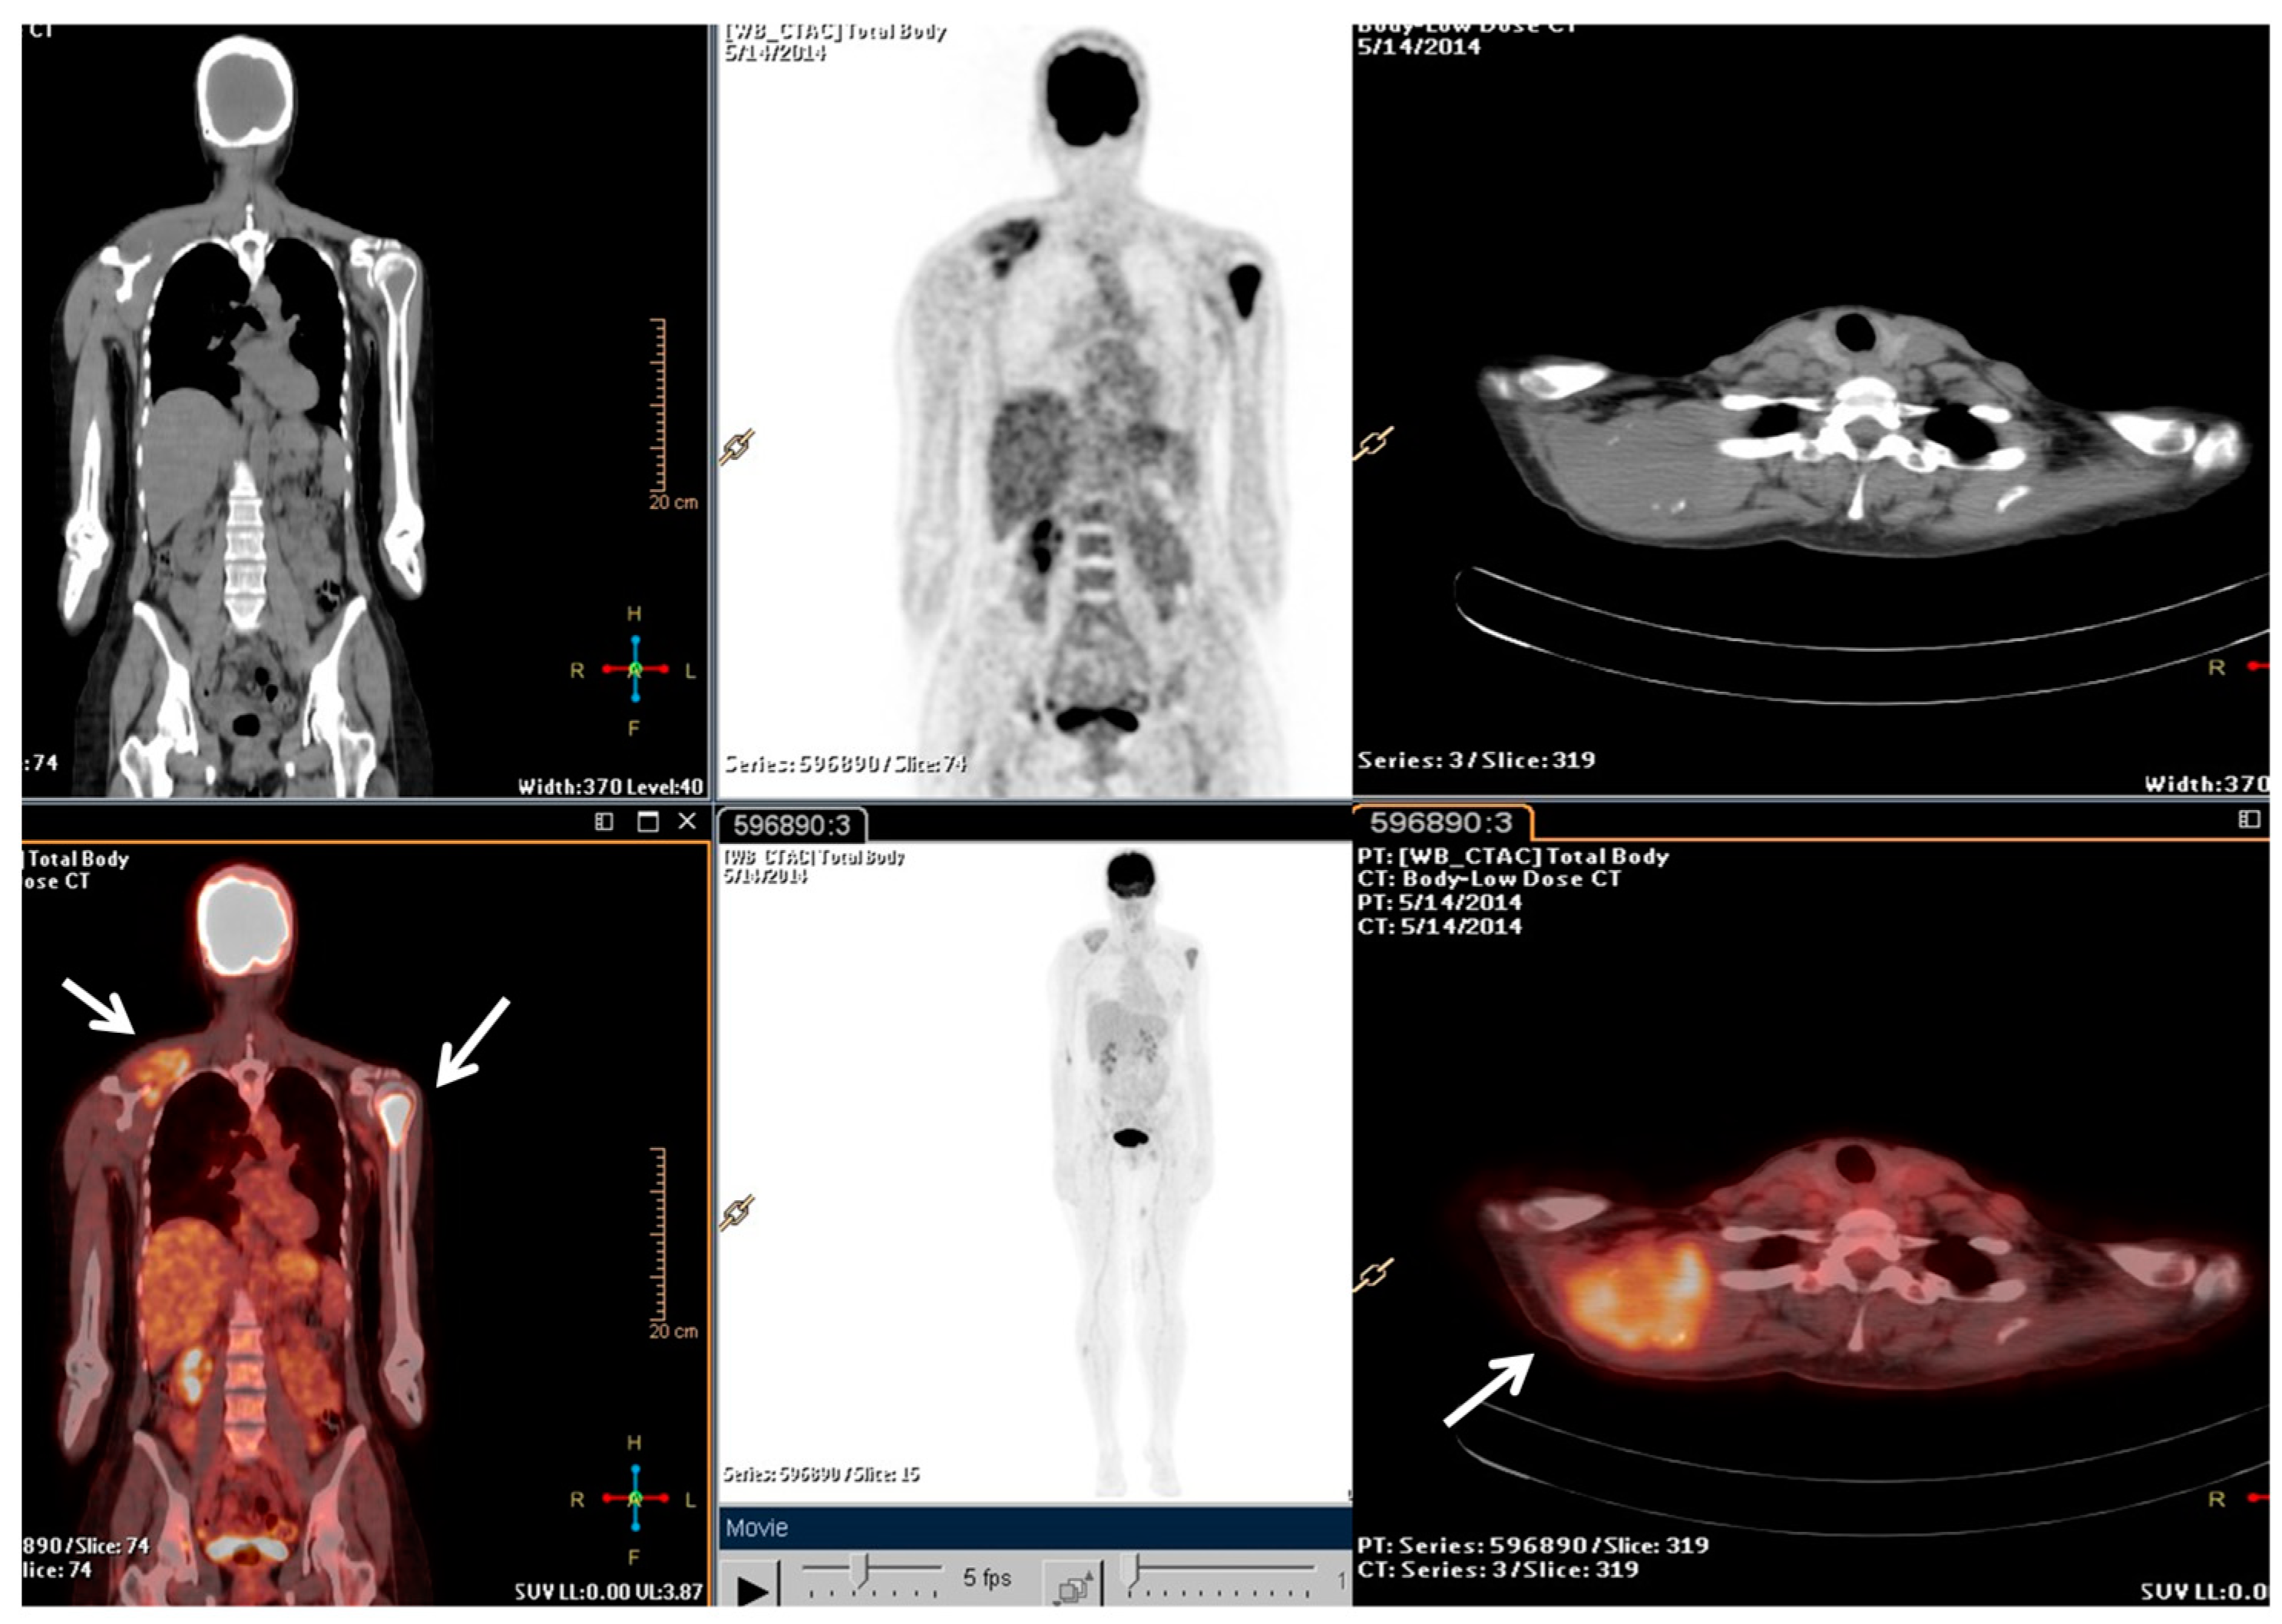

2.2. Clinical Journey of Index Case